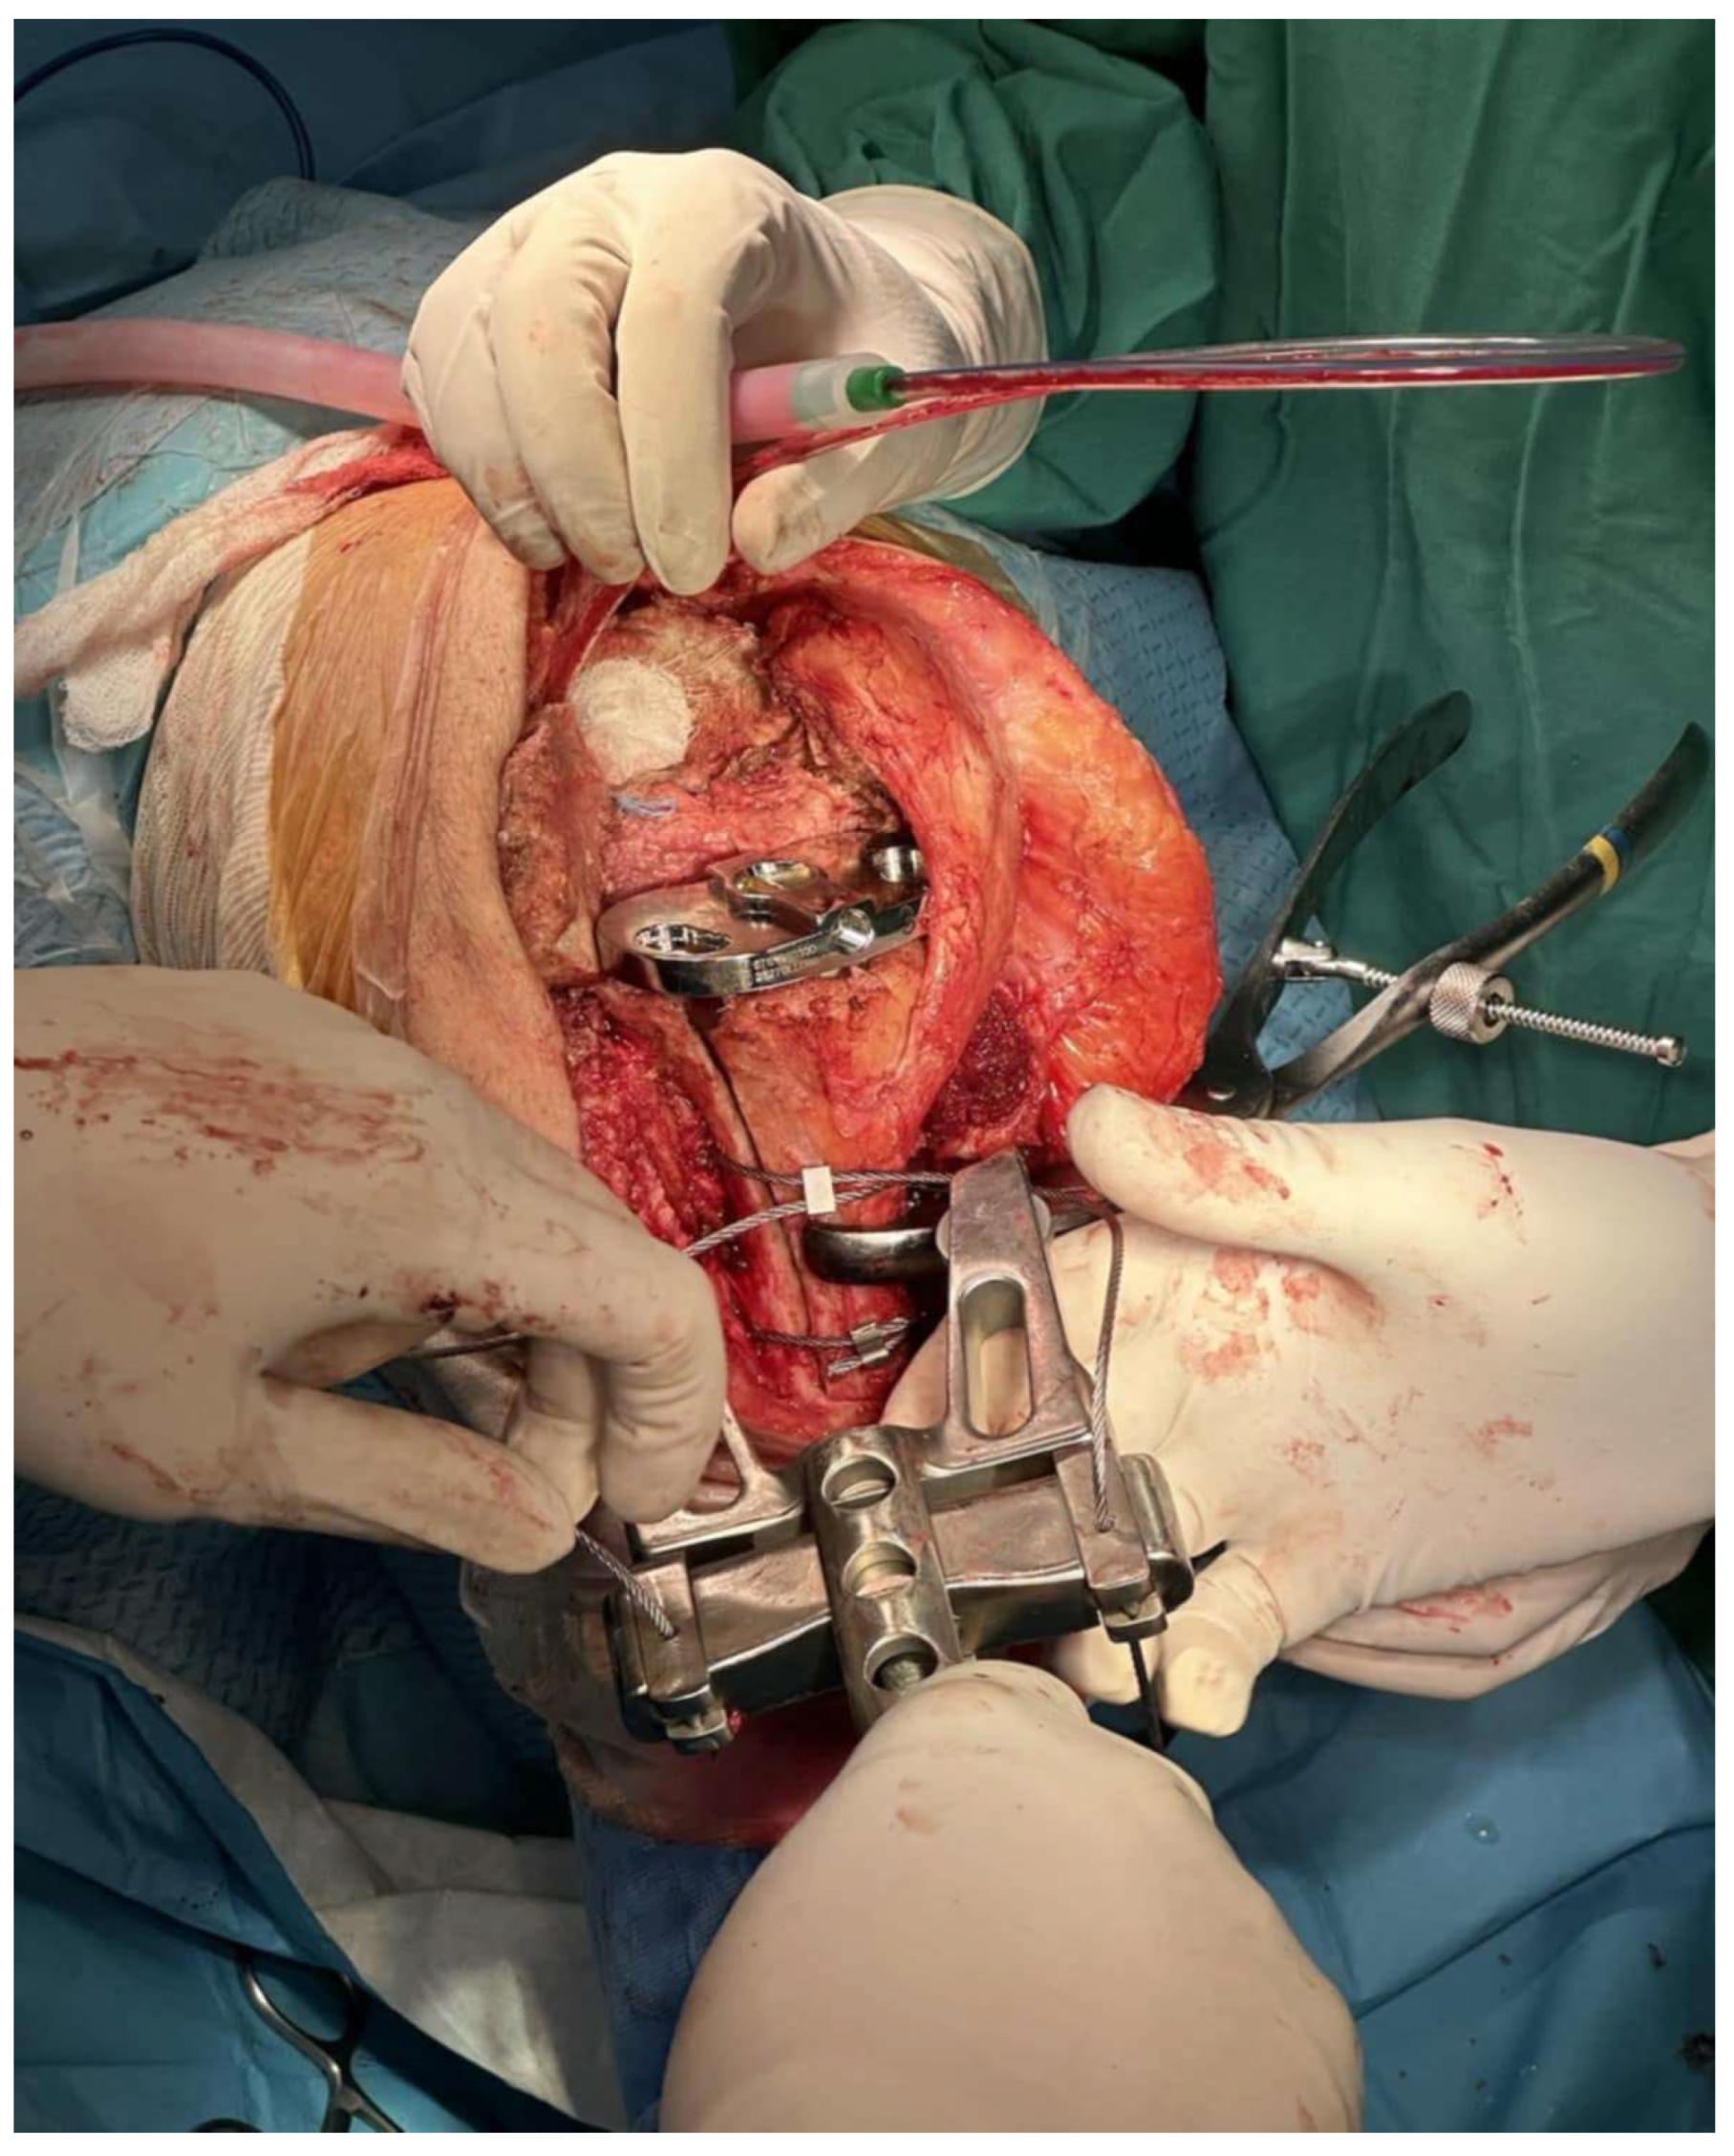

Caution must be given when passing behind the posterior tibia so as not to traumatize the neurovascular bundle. The passer must cross as close as possible to the posterior cortex of the tibia. Afterwards, the tibial component was removed and re-implanted, with bone cement applied solely to the central-metaphyseal region (Figure 3 and Figure 4). Any cement excess was removed from the osteotomy site.

In our technique (Graphical Abstract), we reduce the bone fragment manually, with the final tibial component provisionally in place. If the fragment does not reduce anatomically, we carve the undersurface of the bone fragment with a rongeur or an oscillating saw until a perfect fit is acquired. Afterwards, we pass and tighten the three wires circumferentially, without any drill holes in the tibia, remove the tibial stem, and reimplant it with bone cement applied solely to the central-metaphyseal region. We always check for stability of fragment fixation in a wide range of motion of the knee joint. This technique allows for a near-perfect reduction of the bone fragment in order to achieve the best union results. Any interfering cement in the osteotomy site is also removed for the same purpose. In comparison with other techniques, we do not perform a proximal step cut, and the osteotomy is extended in the knee articular surface. The anterior border of the tibial baseplate acts as a buttress in ETTO proximal migration. In our case series, we did not report any fragment displacement or nonunion. Tibial component rotation is calculated intraoperatively using the center of the ankle joint and the second metatarsal as landmarks, and the tibial stem must of course bypass the distal end of the osteotomy. Furthermore, we retain as much soft tissue in the lateral tibia as possible. We detach only the bare minimum of lateral muscles in order to perform the lateral tibia parallel cut. All these key steps aim at an anatomical and stable reduction of the bone fragment and vascularization preservation, achieving a high union rate.

Figure 3. Final construct with three cerclage wires and final implants. Cement excess is removed from the osteotomy site (Case 3).